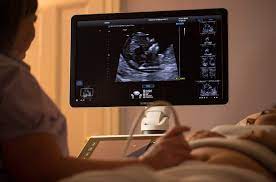

Today ( 8 days later) i called to see when we can expect results. The technicians who take the scans are not trained radiographers and are not trained to interpret the results. The results are read by a radiologist, and the turnaround time for their analysis depends on their availability and where the imaging study was done. If you're pregnant in england you'll be offered an ultrasound scan at around 10 to 14 weeks of pregnancy. You may be asked to breathe in, breathe out, or hold your breath at certain points. A dating scan might be recommended before 12 weeks to confirm your due date if you are unsure of your last menstrual period or your date of conception. This is called the dating scan. I should already have my harmony test results by then so the scan will be used to check for other issues like heart or neural tube problems, since we'll use the harmony results to tell us about. Her gp sent her for a ct scan on the fast track and she had that on 16/11/16. How long does it usually take to get your results back from a cat scan? She waited a further 2 weeks for the results and she was told on 23/11/16 by the respiratory consultant that he thought it was a tumour and it measures 4.3 cm in diameter. The live scan results are either emailed or sent to the requesting agency listed on the request for live scan service form. The scan is optional and not everyone will have it.

'is a scan that uses sound waves to create a picture. It's been more than 15 days since i did my live scan and i still have not received my response? They said the oncologist will give him results at that appointment. The department of justice (doj) usually processes live scan fingerprinting within 72 hours. In terms of results, the consultant may get them in 2 days, but sometimes you need to wait for them to be discussed. During the scan you may be asked to hold your breath at particular times and you will need to lie still. I checked today and his office says nothing yet. Pet scan is coming up for our loved one and we are seeing the doctor right after it's completed. I think scan results take at least 10 days, maybe even a fortnight, but someone else on here may be able to answer that further. The scan will usually take around 10 to 20 minutes. Review microsoft defender antivirus scan results. Is it normal to take that long, should i be worried? The scan may also be part of a screening test for down's syndrome.

The scan will take 20 to 40 minutes.